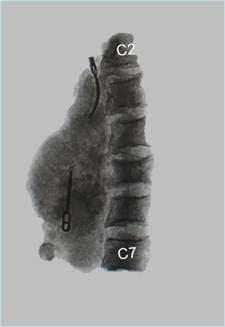

左边为根据小雯术前的颈椎打印的3D模型,图中红色粗管为颈动脉,绿色为肿瘤,白色为颈椎;右边为3D打印的钛合金人工椎体,植入小雯脖内的与图中的几乎相同。